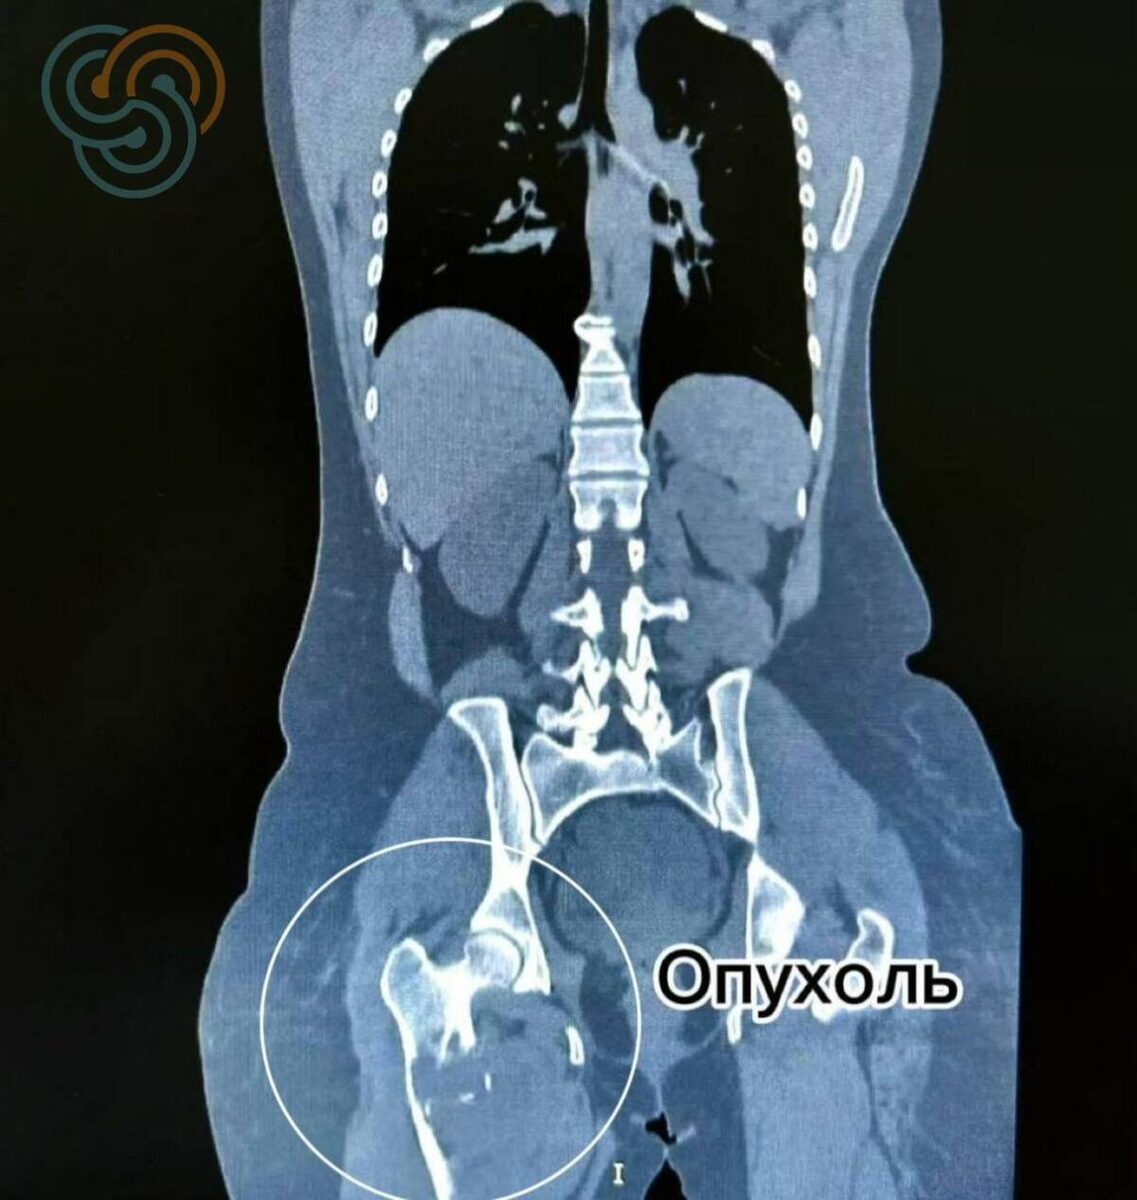

В Татарстане врачи Республиканского клинического онкологического диспансера заменили пациентке бедренную кость, пораженную саркомой. Об этом сообщила пресс-служба медицинского учреждения.

В апреле женщина столкнулась с болью в ноге, которая продолжительное время не утихала. На обследовании был поставлен диагноз «саркома». Во время ожидания результатов анализа биопсии в федеральном центре опухоль разрушала бедренную кость и вскоре произошло одно из самых тяжелых осложнений – патологический перелом. В большинстве подобных случаев пациентам ампутируют ногу.

«Объем поражения был крайне большим – фактически затронута вся бедренная кость. Здесь нам удалось выполнить радикальное хирургическое вмешательство с сохранением конечности», – отметил заведующий онкологическим отделением № 16 Ильдар Сафин.

В декабре была выполнена операция, которая ранее не проводилась в Татарстане: полная замена пораженной бедренной кости с тотальным эндопротезированием тазобедренного и коленного суставов.